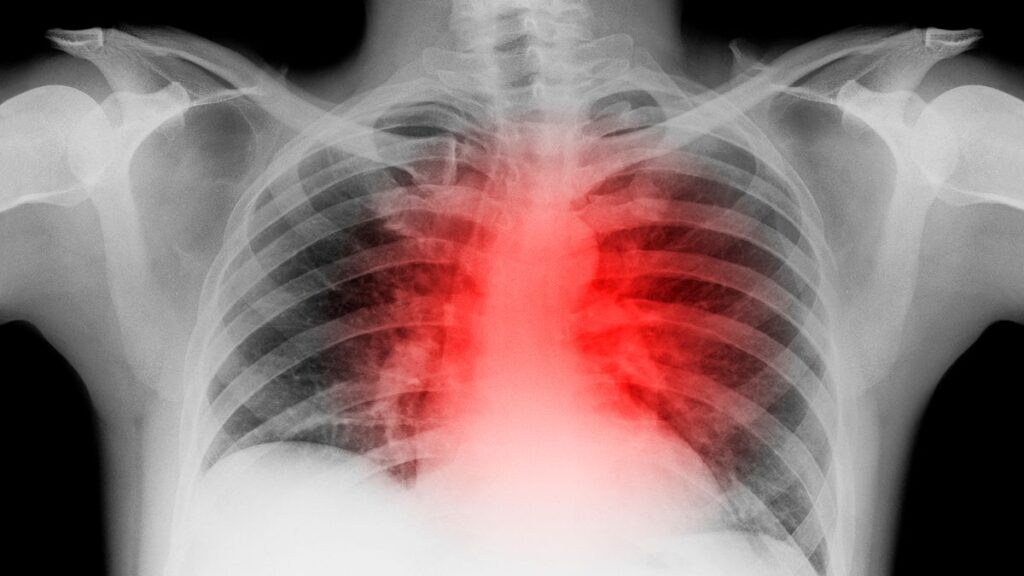

La salud del corazón puede verse afectada, y con efectos duraderos, a consecuencia de la Covid-19, aunque esta puede pasar desapercibida a priori, una vez que el paciente se ha recuperado.

Las secuelas que deja la Covid-19 en el corazón

De hecho, de esos 100 pacientes con Covid-19, 78 todavía tenían signos visuales de que el virus tenía un impacto en el corazón. En concreto, sesenta tenían signos de inflamación continua del músculo cardíaco.

«Eso es realmente convincente», ha declarado a NBC News la Dra. Clyde Yancy, jefa de cardiología en el departamento de medicina de Northwestern Medicine en Chicago. «Indica que meses después de la exposición al COVID-19, aún podemos detectar evidencia de un corazón que no es completamente normal».

El problema puede sin embargo no provocar síntomas físicos, aunque evidentemente podría indicar un riesgo de daño cardíaco adicional.